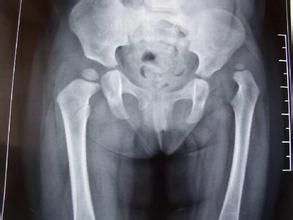

X線檢查 臨床檢查是診斷的第一步,它只能說明髖關節有問題,但最後作出診斷需用X線攝片。嬰兒出生後2~3月內,股骨頭骨骺骨化中心尚未出現,X線檢查乃依靠股骨頸的乾近側端與髖臼關係來測量。骨化中心出現後,攝片包括雙側髖關節的骨盆片可以確定診斷,攝片時將雙下肢併攏,將患肢上推和下拉住各攝一片對比測量,則變化更明顯可靠。測量方法有以下幾種:

(一)連線雙側髖臼Y型軟骨的水平線(稱Y線或Hilgenreiner線),自髖緣外側骨化邊緣的垂線(稱Perkin線或Ombredarne線),兩線交叉將髖臼劃為四區,正常股骨頭骨化中心應在其內下區,若位於其它地區,則為脫位。脫位側骨化中心常較小。

YY′=Y線Hilgenreiner線;EP、E′P′=Perkin線;虛線=Shenton線(健側相連續)